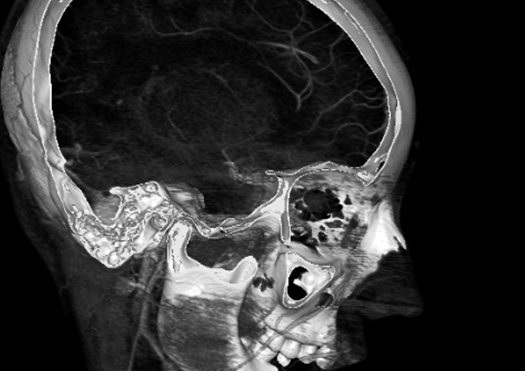

Tomografía

La Tomografía Computarizada (TC) es una reconstrucción computacional de un plano tomográfico (una rebanada) de una región anatómica. Se realiza proyectando un haz de rayos X alrededor del paciente con un sistema Helicoidal para medir la cantidad de radiación que logra salir de los tejidos del paciente, organizando dicha información en imágenes seccionales paralelas y consecutivas en grandes volúmenes que permiten realizas reconstrucciones en 2D y 3D.